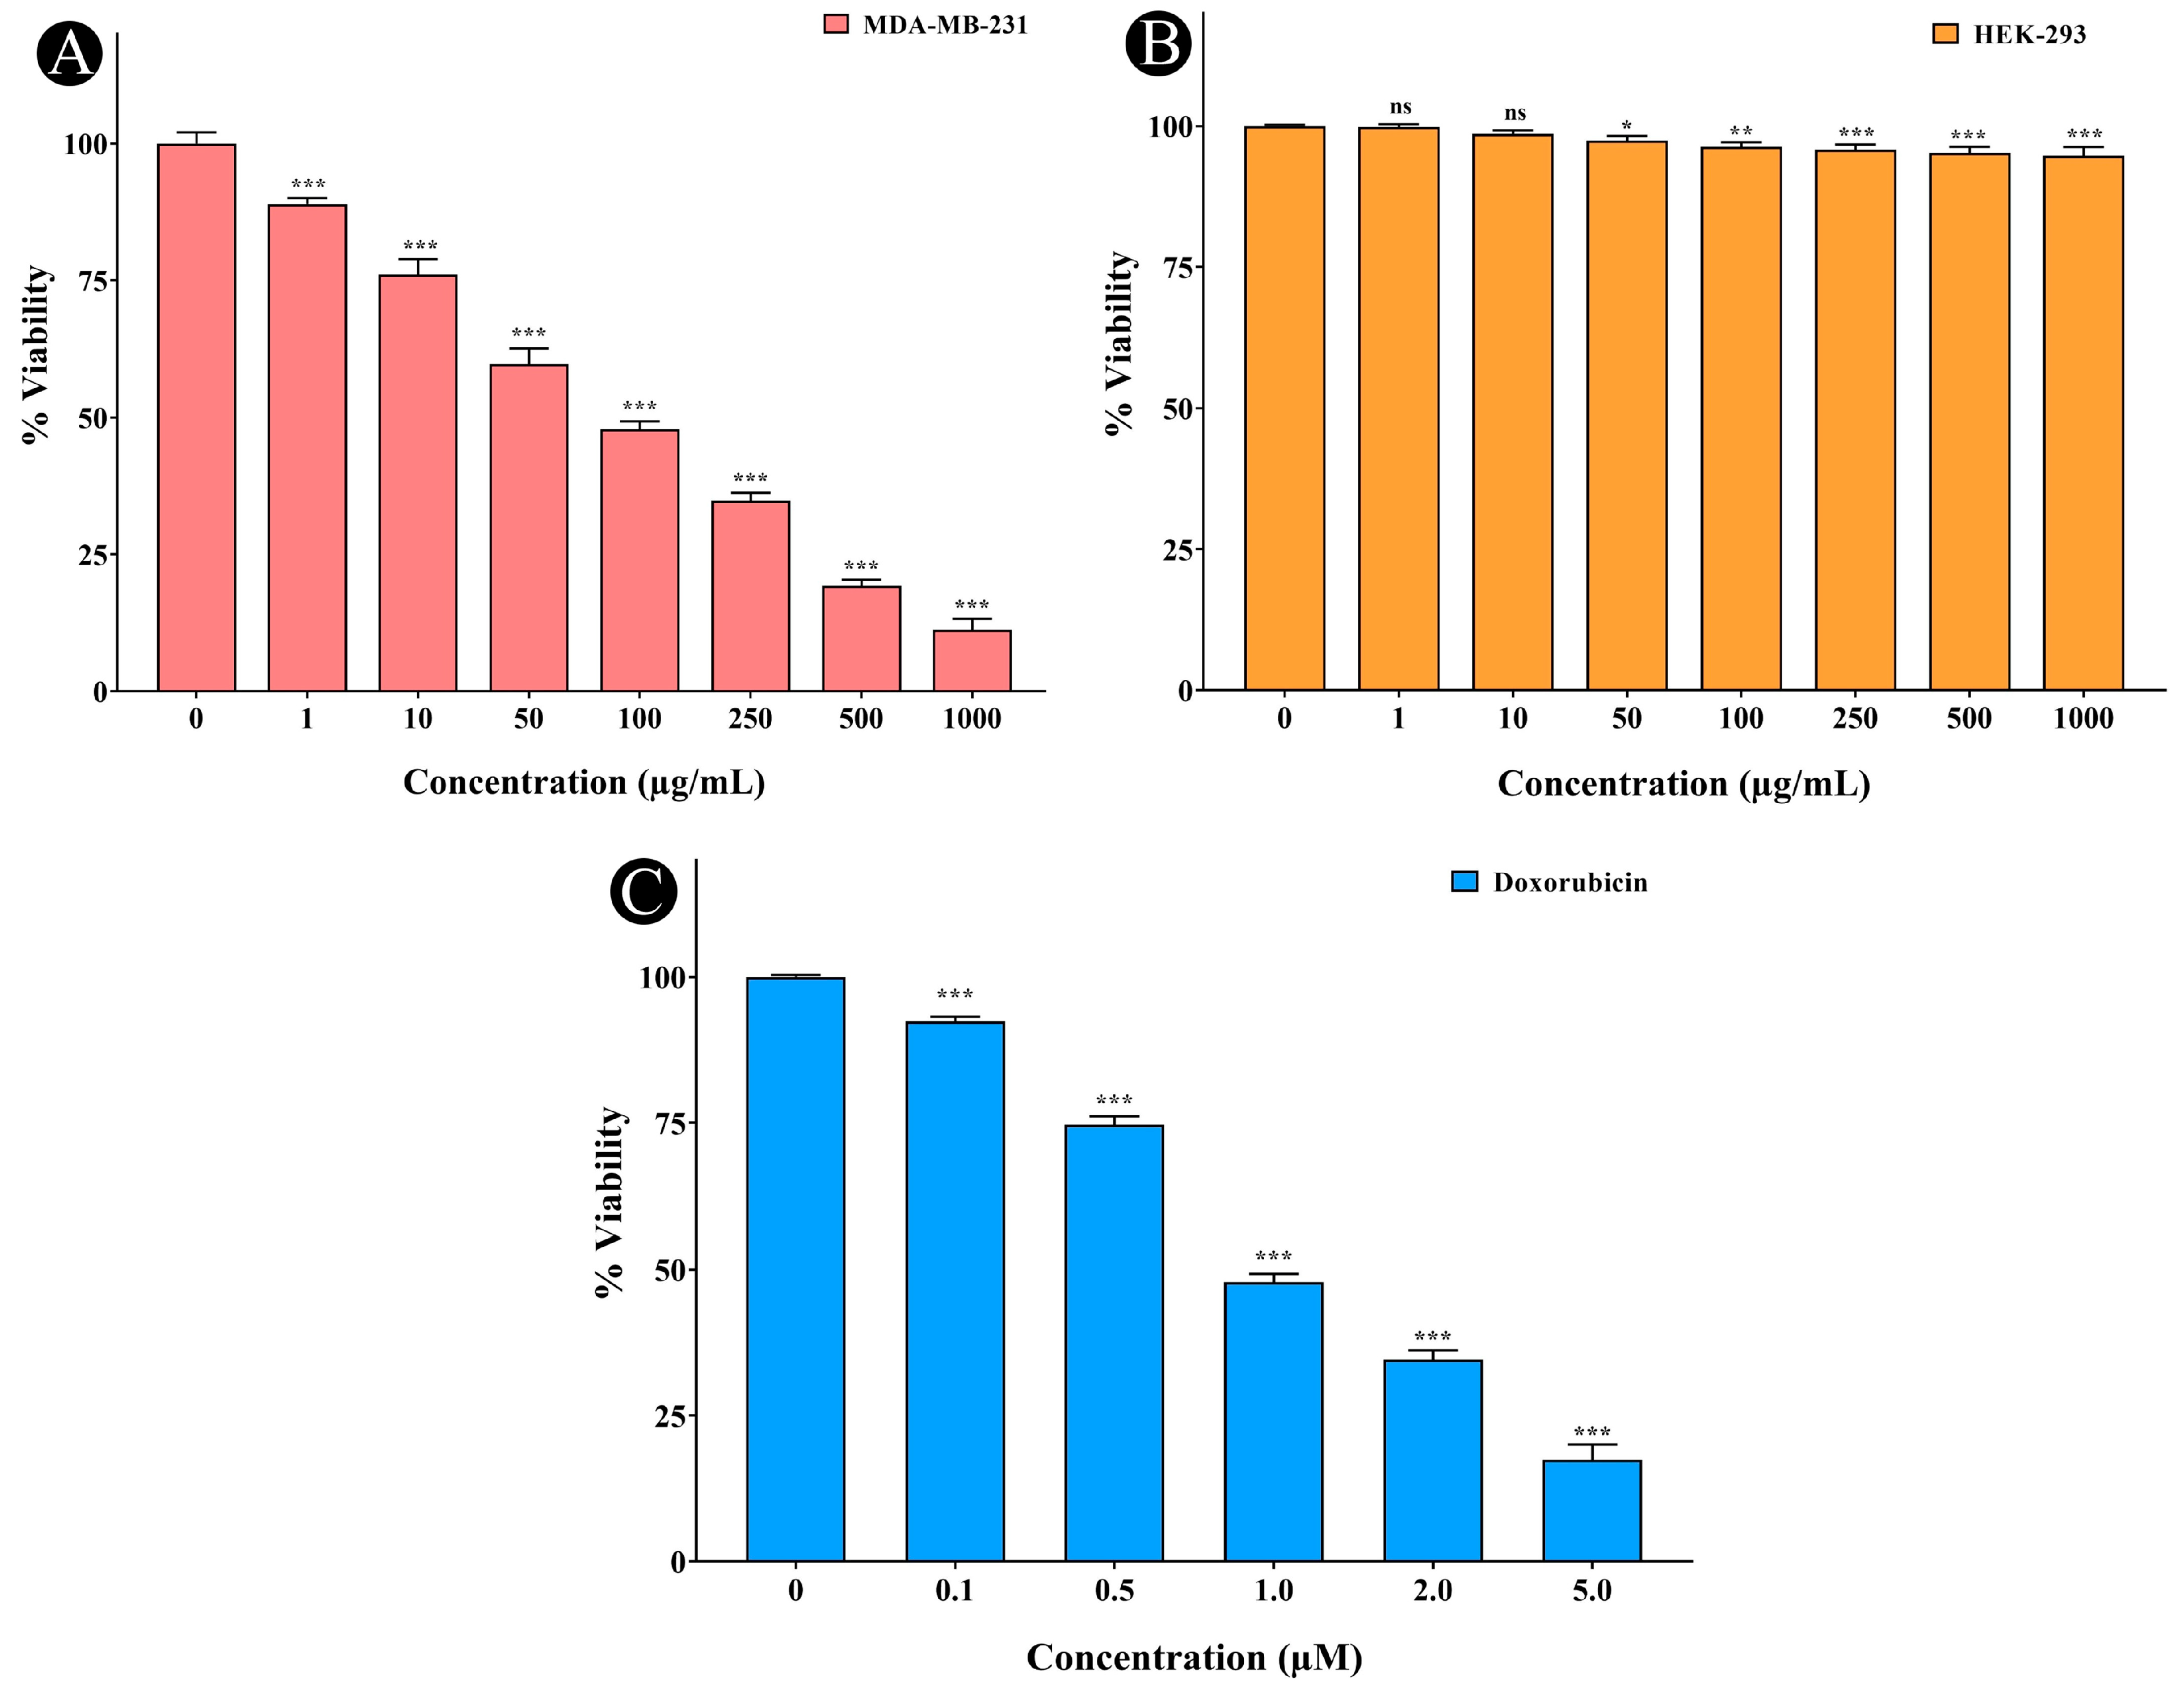

2.7. Anticancer Activity of A. racemosus Crude Extract